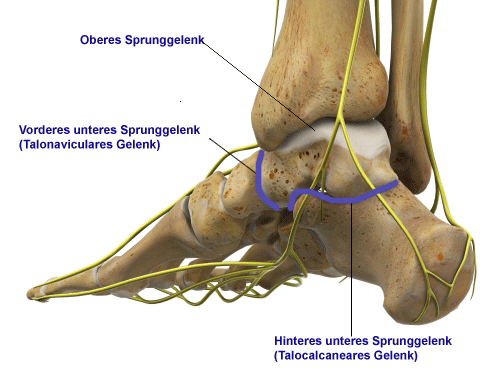

Aufbau des unteren Sprunggelenks

Es werden zwei Sprunggelenke unterschieden:

- Oberes Sprunggelenk (kurz OSG) zwischen Sprungbein und Schienbein bzw. Wadenbein

- Unteres Sprunggelenk (kurz USG) gebildet aus Sprungbein, Fersenbein, Kahnbein und Würfelbein

Wie ist das untere Sprunggelenk aufgebaut und welche Funktion hat es?

Das untere Sprunggelenk ist deutlich komplexer aufgebaut als das obere Sprunggelenk. In diesem mehrteiligen Fußgelenk stehen Sprungbein (Talus), Fersenbein (Calcaneus) sowie Würfelbein (Os cuboideum) und Kahnbein (Os naviculare) in Kontakt. Sie regulieren die Stellung des Fersenbeines und Rückfußes nach Innen oder Außen bei unebenem Untergrund.

Die Freiheitsgrade der Bewegung im unteren Sprunggelenk gleichen besonders beim Stehen und Gehen auf schiefem oder unebenem Gelände durch Beweglichkeit des Fersenbeines diese Unebenheit aus. Vor allem beim Laufen spielt diese Beweglichkeit auch eine wichtige Rolle bei der Dämpfung des Aufpralls durch das Fußgewölbe. Dabei kann das Fersenbein Unebenheiten ausgleichen durch seine Beweglichkeit nach innen um maximal 30° (Inversion) und nach außen um maximal 15° (Eversion).